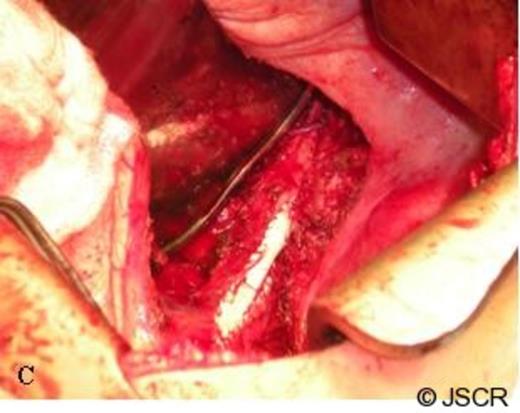

The second stage of the procedure was carried out through double thoracotomy incisions – a thoracotomy through the 5th intercostal space for resection of her pulmonary metastases and an additional thoracotomy through her 8th intercostal space to provide adequate exposure for retroperitoneal dissection of her right adrenal gland. Following the wedge resections of her right lung metastases, dissection was begun to resect the right adrenal gland. A firm mass was palpable prior to incising the diaphragm, and it appeared that the adrenal metastasis had invaded the diaphragm locally. A 3cm x 3cm portion of diaphragm was incised and dissection was carried down around the liver and the adrenal mass was excised from the caudate lobe. The cancer was noted to be invading the wall of the IVC, and therefore, a vascular surgeon was consulted to assist in completion of the resection. Proximal and distal control of the IVC was obtained (Figure 1).

Dissection of the caudate lobe of the liver to gain proximal and distal control of the IVC. The tumor is being retracted cephalad with a clamp.